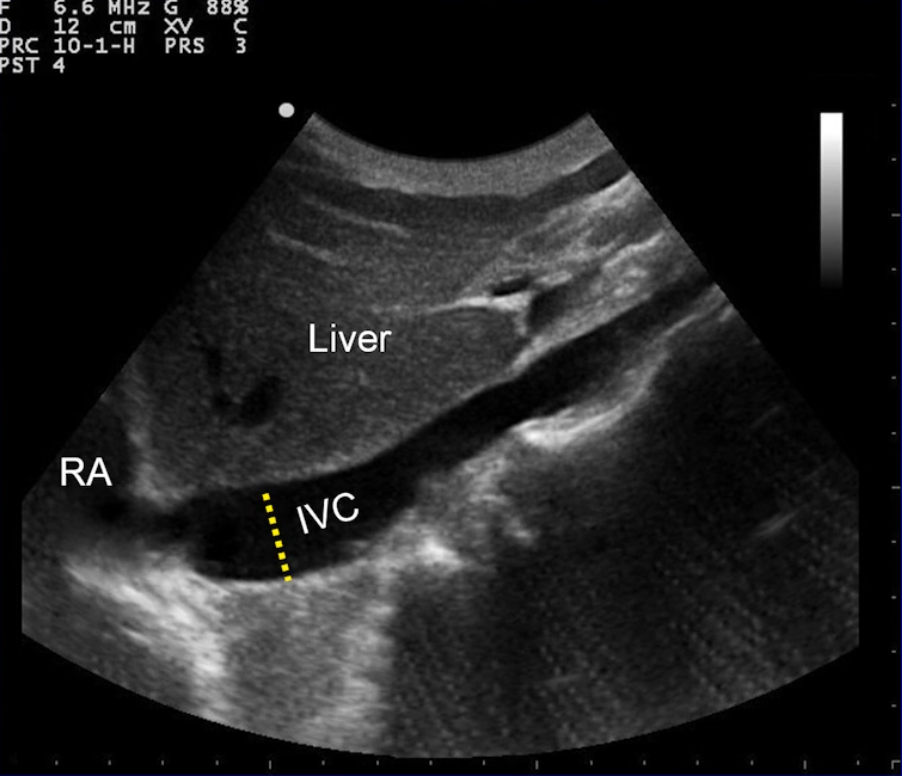

- Bedside ultrasound

- Place in subxiphoid/subcostal area and orient head to toe

- Measure the IVC diameter and collapsibility with sharp inspiration (ask the patient to ‘sniff’)

- Collapsibility of IVC with inspiration